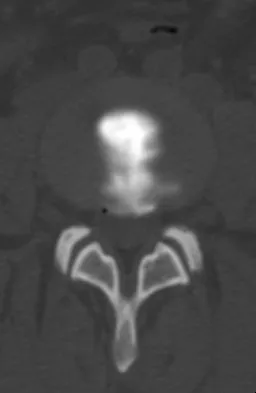

A patient is treated with volar plating for a distal radius fracture. The CT scan shown in Figure 15 is obtained after union of the fracture because the patient reports ongoing symptoms. The prominent hardware is most likely injuring what tendon?

Extensor tendon injuries have been reported after volar plating of distal radius fractures. The CT scan shows prominent dorsal hardware a few millimeters ulnar to Lister's tubercle. The second compartment, the ECRL and ECRB, is radial to Lister's tubercle. The ECU runs along the distal ulna. The contents of the fourth dorsal compartment run just ulnar to Lister's tubercle. The EDC tendon is likely irritated in this patient. The EPB runs along the radial border of the radius and is well away from prominent hardware. Benson EC, Decarvalho A, Mikola EA, et al: Two potential causes of EPL rupture after distal radius volar plate fixation. Clin Orthop Relat Res 2006;451:218-222.

- Cooney WP, Linscheid RL, Dobyns JH (eds): The Wrist: Diagnosis and Operative Treatment. Philadelphia, PA, Mosby-Year Book, 1998.